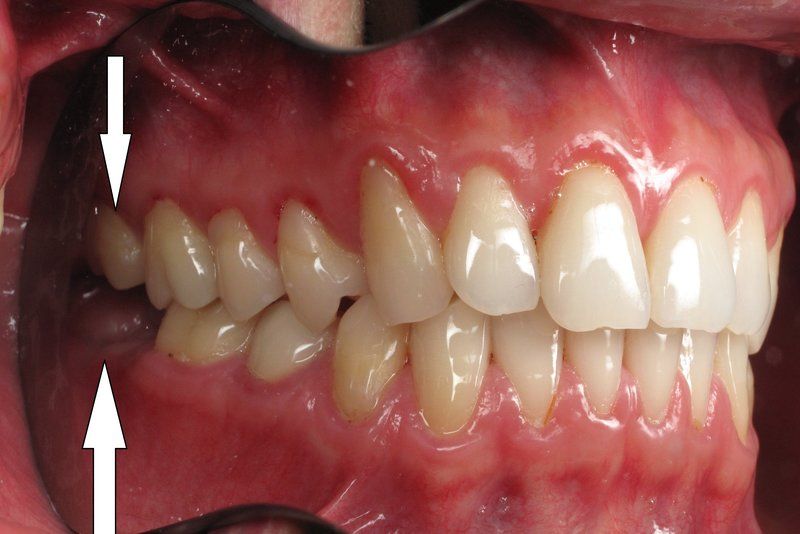

Răng khôn hay còn gọi là răng số 8 là chiếc răng mọc cuối cùng trong cung hàm, ở những người trong độ tuổi từ 18 đến 28. Chiếc răng này thường gây ra rất nhiều phiền toái. Theo thống kê thì có tới 70% người cần nhổ răng khôn. Trải qua vài triệu năm tiến hóa của loài người từ loài vượn người, hàm của con người ngày càng nhỏ hơn, và phần lớn thời gian chỉ đủ chỗ cho 28 chiếc răng với 14 chiếc răng hàm trên và 14 chiếc răng hàm dưới. Do đó, vấn đề là răng khôn không đủ chỗ để mọc theo hướng bình thường trong cung hàm, đây chính là nguyên nhân dẫn đến tình trạng răng khôn mọc lệch, mọc ngầm. Những trường hợp trên bác sĩ thường chỉ định nhổ răng khôn tránh để lại những biến chứng nguy hiểm và giúp người bệnh giải quyết những khó khăn trong cuộc sống hàng ngày.

Nhiều người lo lắng không biết nhổ răng khôn hàm trên có nguy hiểm không. Trên thực tế, những lo ngại này là hoàn toàn chính đáng. Nhưng khi mọc răng khôn hàm trên hay răng khôn hàm dưới thì đều có vấn đề. Tất cả các vấn đề phải được loại bỏ để tránh biến chứng trong tương lai.